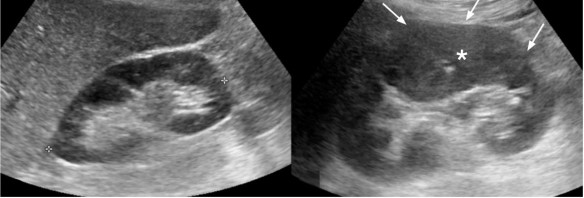

Hình 1.4. Hình ảnh sỏi niệu quản đoạn 1/3 trên kèm theo thận ứ nước

(Nguồn: Nicolau C., 2015) [131]

Hình 1.5. Bệnh nhân nữ 42 tuổi đau vùng thắt lưng bên trái và sốt. Siêu âm có hình ảnh thận trái lớn (hình bên phải) với tăng âm ở vùng vỏ (mũi tên với dấu hoa thị) so với thận bên phải (hình bên Trái). Dấu hiệu hình ảnh này gợi ý là phù nhu mô thận do viêm

(Nguồn: Sim K.C.,2018) [161]